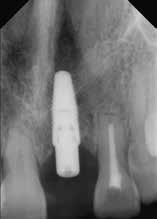

Der Patient wurde im Zuge der Tumornachsorge wieder an der Universitätszahnklinik Wien vorstellig. Am Beginn der prothetischen Fallplanung wurden montierte Situationsmodelle erstellt und ein aktueller Röntgenstatus erhoben. Intraoral bestätigte sich, dass der resezierte Bereich mittels eines Zungentransplantates gedeckt wurde.

Da der Patient bereits bestehende alte

Modellgussprothesen für den Oberkiefer und den Unterkiefer hatte, wurden diese herangezogen und als Immediatersatz erweitert sowie unterfüttert. Während der Planung entschied sich das behandelnde Ärzt:innen-Team sowohl im Ober- als auch Unterkiefer für eine teleskopierende Metallgerüstprothese. Zahn 11 wurde mittels Adhäsivtechnik aufgebaut und darüber hinaus für Zahn 21 eine Einzelzahnzirkonkrone geplant. Um eine adäquate Retention der Kronen gewährleisten zu können, wurden an fünf Zähnen gegossene Stiftaufbauten eingegliedert (Abb. 6 u. 7).

Abb. 6: Intraorale Ansicht Unterkiefer nach Tumorresektion, Deckung mit Zungenlappen und nach Beschliff

Abb. 7: Intraorale Ansicht Oberkiefer nach Beschliff

Nach erfolgter Meisterabformung beider Kiefer erfolgte eine Überabformung der angefertigten Transferkäppchen mit einem individuell angefertigten Abformlöffel. Somit konnte dem zahntechnischen Labor eine präzise Schleimhautabformung zur Verfügung gestellt werden. Insbesondere wurde dabei auf die Detailtreue des resezierten Bereiches im Unterkiefer geachtet.

Anschließend an die Bissnahme mittels Bissschablonen und die gemeinsame Begutachtung der

Wachsaufstellung (Abb. 8–10) erhielt das zahntechnische Labor die Freigabe zur Erstellung der Primärund Sekundärteleskope mit Gerüsten. Diese wurden insbesondere auf ihre Passgenauigkeit und Schaukelfreiheit im Kiefer überprüft. Des Weiteren wurde bei der Erstellung auf eine Unterspülbarkeit des transplantierten Gebietes geachtet. Nach erfolgter Wachsaufstellung auf Gerüst wurde die Fertigstellung der Teleskopprothesen und der Einzelzahnzirkonkrone in

Auftrag gegeben. Für Zahn 11 wurde vom zahntechnischen Labor ein entsprechendes Mock-up mit Schiene zur Übertragung erstellt (Abb. 11–23). Anschließend an die komplikationslose Eingliederung der Arbeit erfolgte eine Kontrolle sieben Tage nach erfolgter Übergabe (Abb. 24, Seite 7). Nach der Durchführung von minimalen Korrekturen an der Okklusion wurde der Patient in den Recall entlassen.•